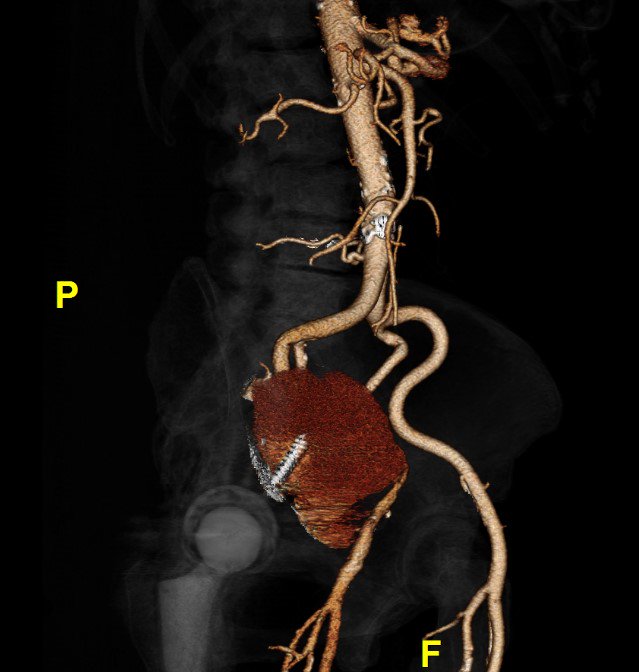

A month earlier, she’d been found to have a large pseudoaneurysm arising from her external iliac artery. (And yes, that’s a screw from a previous hip replacement traversing it.) She underwent stenting and returned home.

Because she was septic and in pain, we scanned her again. The new CT showed extensive gas within the pseudoaneurysm. It was now infected, and that was a big problem.